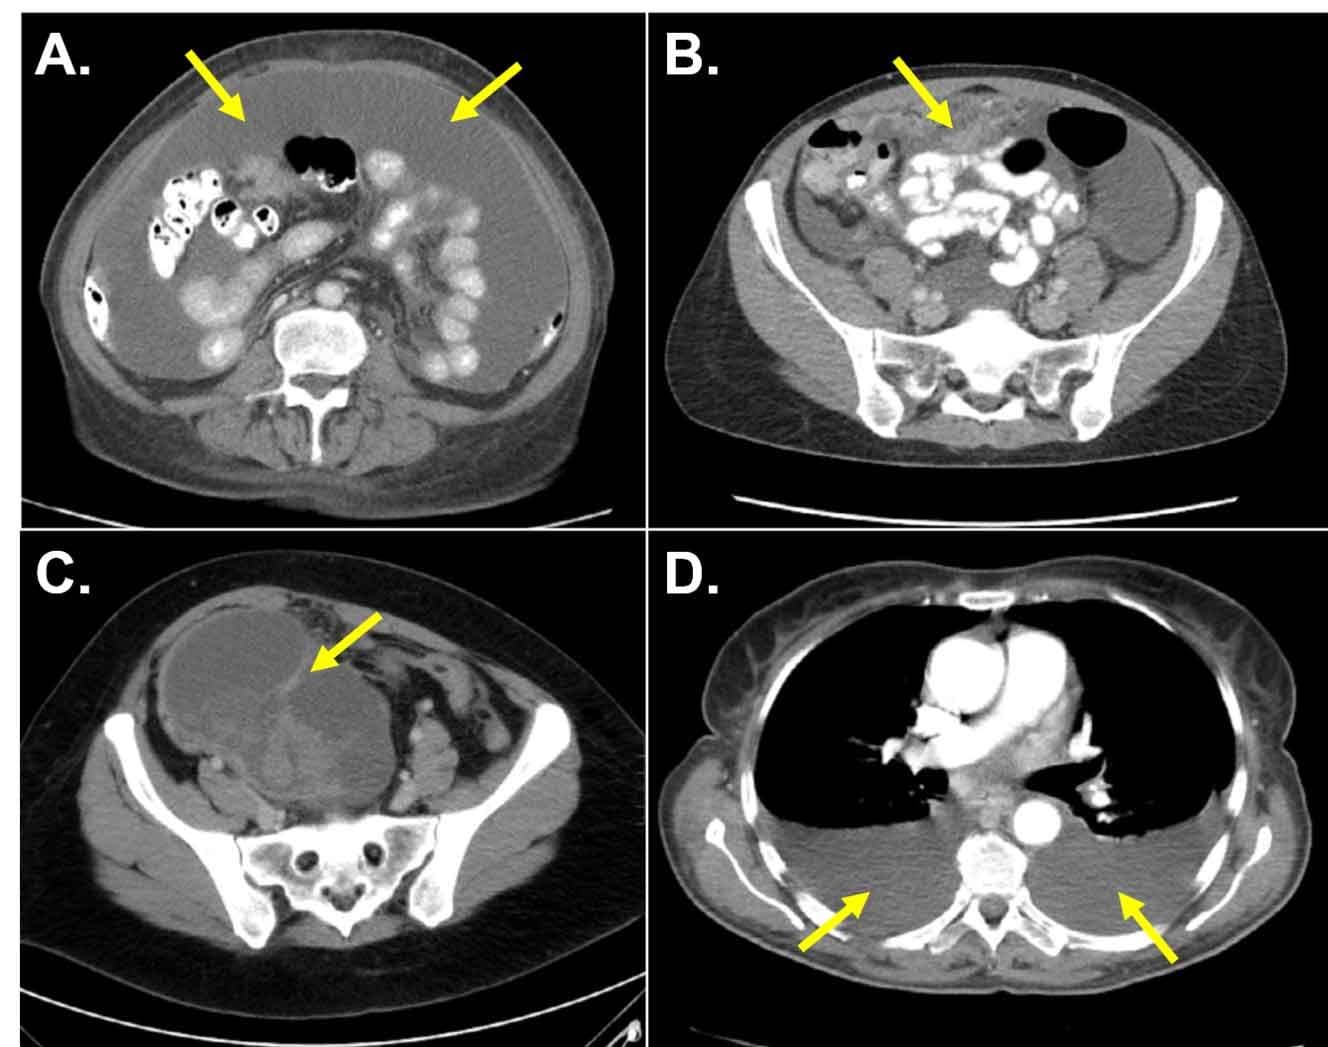

Figure 3. Common radiographic findings for advanced-stage ovarian cancer

A. Large-volume abdominal ascites.

B. Bulky omental disease (“omental caking”)

C. Complex pelvic mass with cystic and solid components

D. Bilateral moderate/large malignant pleural effusions

Ovarian cancer commonly spreads along peritoneal surfaces involving the bowel, omentum and adjacent structures. In general, symptoms related to ovarian cancer are vague and manifest late in the disease process. While not specific to ovarian cancer, symptoms include sub-acute onset of abdominal/pelvic/back pain, fatigue, abdominal bloating, constipation or urinary symptoms.[90–92] Weight loss is less common, as the majority of patients will develop abdominal ascites (Figure 3). While most patients present with several months of worsening symptoms, some patients will present with acute symptoms. Patients with moderate or large malignant pleural effusions may present with shortness of breath or a new oxygen requirement (Figure 3). It is estimated that 8-30% of patients with newly-diagnosed ovarian cancer will present with a malignant bowel obstruction. Malignant bowel obstruction at the time of diagnosis is associated with a decrease in PFS and OS.[93] Fewer than 1% of patients present with a venous thromboembolism (VTE) at the time of initial ovarian cancer diagnosis. In the setting of a deep vein thrombosis (DVT), symptoms may include leg pain or swelling. Symptoms related to a pulmonary embolism (PE) may include chest pain, shortness of breath and/or cough.[94] Patients with early stage disease may present with symptoms described above, but are more likely to be asymptomatic.

Because symptoms often develop late in the disease process, the majority of women with ovarian cancer present with disease spread beyond the ovary and with advanced-stage disease (>70%). Frequently, disseminated ovarian cancer will be found on CT or US imaging ordered for non-specific symptoms or other indications (Figure 3).[117] As the presentation of other advanced-stage malignancies (e.g. pancreatic cancer, colon cancer) can be similar to patients with disseminated ovarian cancer, tissue confirmation is required prior to moving forward with a treatment plan (i.e. surgical resection and/or chemotherapy). Tissue confirmation can be achieved at the time of surgical exploration or via image-guided biopsy.